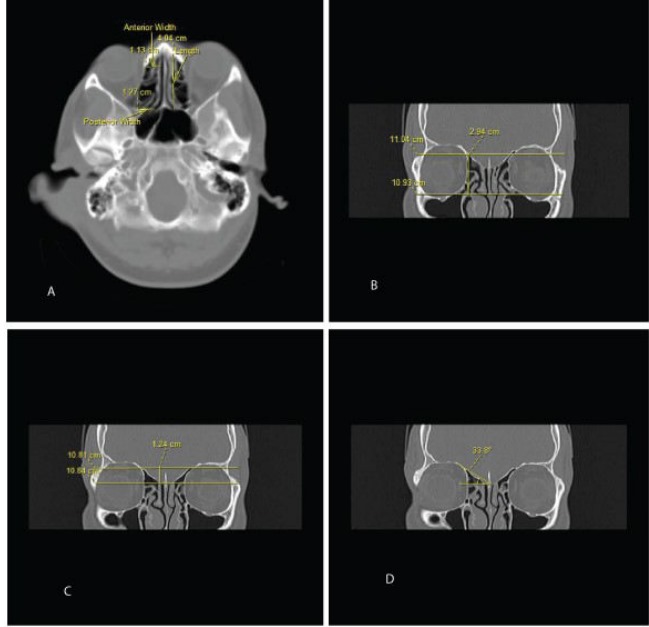

- Otorhinolaryngology

- Care Image Processing

- Healthcare Research